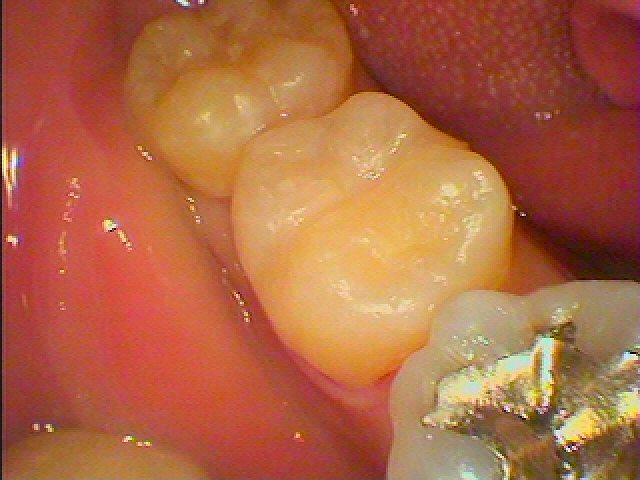

問題の歯になります

この銀歯を外していきます